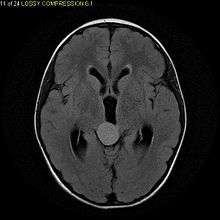

Pilocytic astrocytomas are often cystic, and, if solid, tend to be well-circumscribed. It is characteristically easily seen on CT scans and MRI.

Usually—depending on the interview of the patient and after a clinical exam which includes a neurological exam, and an ophthalmological exam—a CT scan and or MRI scan will be performed. A special dye may be injected into a vein before these scans to provide contrast and make tumors easier to identify. The neoplasm will be clearly visible.

Visual aspect

Macroscopically, an astrocytoma is a mass that looks well-circumscribed and has a large cyst. The neoplasm may also be solid.